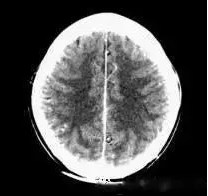

(機器故障偽影:常為環形或同心圓狀高密度偽影)

2、機器故障偽影的形狀機器故障所至偽影的形狀各種各樣,有非同心圓形和同心圓形(單同心圓和多同心圓、直線形、柵格形條紋狀)、星狀,還有不規則形,一般來說.根據偽影形狀可大致區分為機器哪一個系統故障所致。